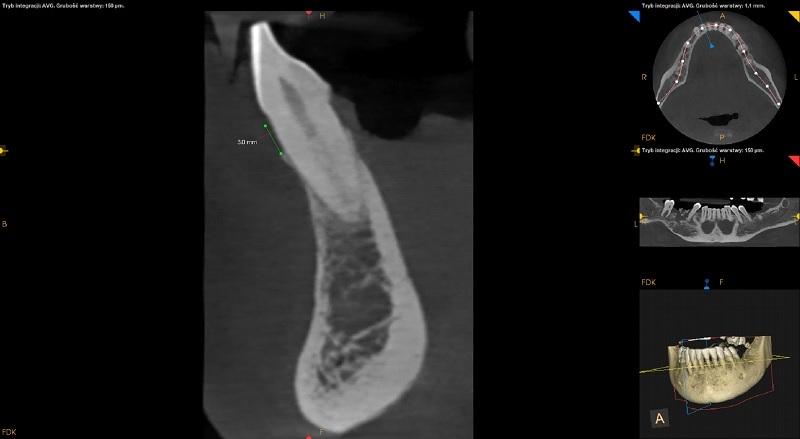

W zatoce szczękowej prawej widoczna rozległa zmiana z obwodowym zwapnieniem o wymiarach około 28mm x 28mm x 29mm. Zmiana modelująca, widoczne znaczne uwypuklenie ściany bocznej z rozległym ubytkiem ciągłości (około 16mm). Przerwanie ciągłości dna zatoki w okolicy 16. Ściana przyśrodkowa zatoki lekko wymodelowana, ciągłość zachowana. Hiperostoza ściany bocznej prawej zatoki powyżej zmiany. Do konsultacji laryngologicznej i dalszej diagnostyki.

Pozostawione korzenie resztowe zębów 18 i 16. Wierzchołek korzenia zęba 16 w świetle zmiany.